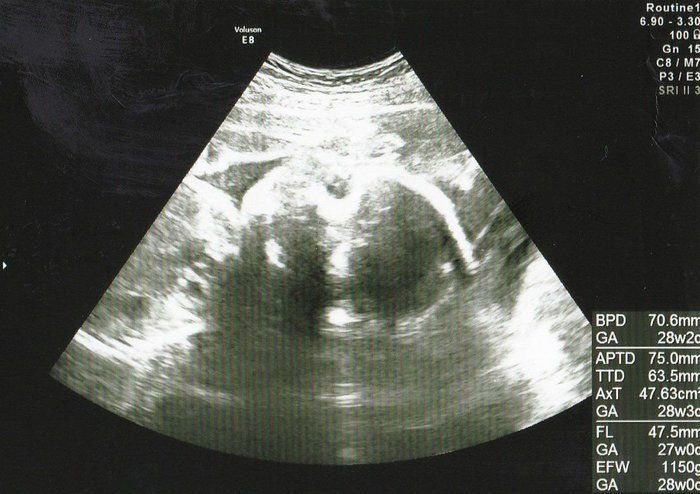

【妊娠26週】赤ちゃんのエコー写真・超音波写真まとめ

ママライターのみなさんの妊娠出産体験談から妊娠26週の赤ちゃんのエコー写真を集めました。

かえるさんの妊娠26週目のエコー写真

女子とほぼ確定しました。少し大きめらしく、ドキドキ。妊娠6カ月で里帰り先で健診。いろんな検査を一気に受ける中で、軽い“妊娠糖尿病”だと指摘され、自己採血検査を1週間続け、食事指導を受けました。胎動に励まされていましたが、今から思えば、「少し気をつけて食事してね」くらいの意味合いだったはずなのに、かなりストイックな糖質制限をして、がんばって散歩を続けました。真面目すぎる妊婦でした。